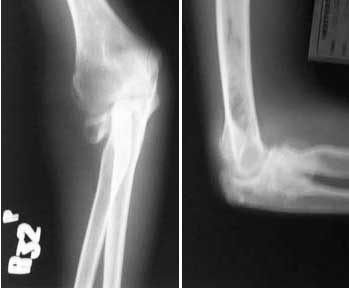

14 year old boy presented with pain and deformity of right elbow. History of injury to right elbow four years back for which he was operated and immobilised in an above elbow cast.

Examination showed surgical scar posterolateral to proximal forearm. Minimal tenderness and crepitus over the radial head area. Cubitus valgus present. Movements: Terminal flexion and extension limited. Last 30 degrees of supination and 20 degrees of pronation restricted. Forearm shortened by 2cm and radial styloid proximal by 1 cm compared to opposite side.

Patient had an immediate post op x-ray which showed a well positioned radial head in a pop cast. Present clinical picture and x-ray attached.

With AVN evident already (if it really is---pictures weren't great quality) ORIF likely will be slow to heal and patient may remain symptomatic secondary to the AVN even if healing occurs. Resection of the radial head after maturity likely to relieve pain but will result in some loss of strength

I am bothered by some of the other radiodense and radiolucent areas on the x-ray - INFECTION is certainly one important thing that can cause nonunion to occur. The additional question is how much AVN is also present in this particular patient.